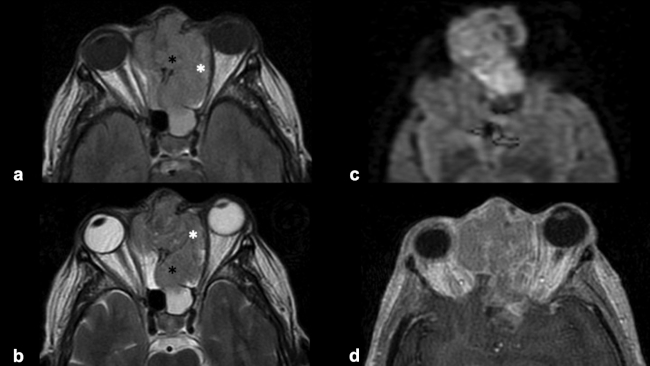

La RM es la prueba de imagen de elección para evaluar los detalles de la extensión y la estadificación locorregional del tumor. La RM es superior a la TC para determinar el grado de afectación del tejido blando (►Fig. 9) con una mejor evaluación de la afectación intracraneal (►Figs.10,11,12,13,14), orbital (►Figs.14y15), de la base del cráneo y la invasión perineural.53,54 La RM tiene un valor añadido para distinguir la afectación dural de la del parénquima cerebral (►Fig. 12).55 En la RM, el NBO aparece hipointenso respecto a la sustancia gris en imágenes ponderadas en T1 y de isointenso a hiperintenso en las imágenes ponderadas en T2 (►Figs.10,11,12,13,14,15).56 Muestra un realce homogéneo, excepto en áreas con hemorragia o necrosis. Además, permite diferenciar las secreciones retenidas del tumor, al ser estas hiperintensas ponderadas en T2.53,55 Los hallazgos de imágenes clásicos incluyen una masa “en forma de mancuerna” que se extiende a través de la placa cribiforme (►Fig. 12), con la parte estrecha a nivel de la placa. Los quistes tumorales periféricos (►Figs.5b,12,14,16) y las calcificaciones moteadas son bastante característicos de NBO.1

Las secuencias de RM con saturación de la grasa ayudan a diferenciar el tumor de la grasa orbital y los músculos. Un margen suave de la interfaz tumor-grasa sugiere que la lesión está contenida en la fascia periorbital (►Fig. 15), mientras que un margen irregular favorece la invasión franca de la órbita.35,49,57 Sin embargo, el diagnóstico definitivo de invasión de la duramadre y los tejidos periorbitarios solo es posible en la cirugía.49

La evaluación del tumor recurrente debe incluir tanto TC como RM. Las características de imagen del tumor recurrente no difieren de su apariencia en la presentación inicial. Se ha sugerido el siguiente protocolo de seguimiento para detectar precozmente las recurrencias: RM con contraste 2-4 meses después de completar todo el tratamiento. Posteriormente, se repite cada 4-6 meses durante 5 años, y pasado ese tiempo, se realiza anualmente durante la vida del paciente.59 El protocolo de RM utilizado en nuestro servicio consiste en la realización de secuencias ponderadas en T1, T2 y T1 con supresión grasa sin y con contraste para el estudio a nivel nasosinusal y secuencias ponderadas en T1, T2, FLAIR, DW-EPI y T1 con contraste para el estudio encefálico. Además, se debe hacer una radiografía de tórax anual para excluir la presencia de metástasis.59